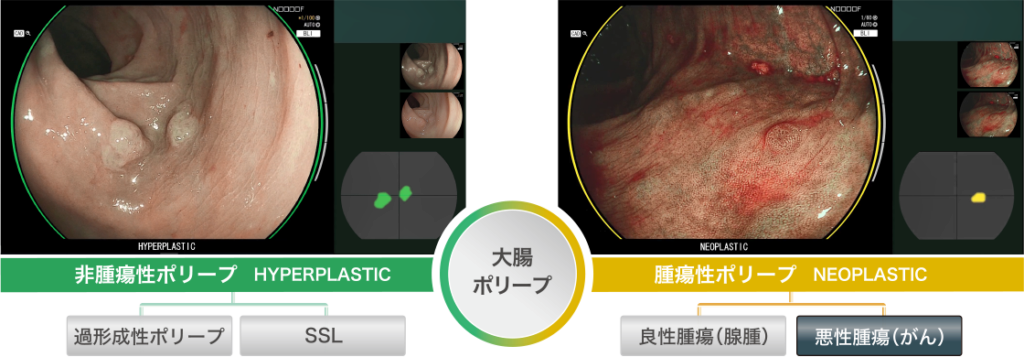

4色のLED光源搭載の富士フィルム社内視鏡システム『ELXEO(エルクセオ)』を導入しています。

照射した光と画像処理を組み合わせる「マルチライトテクノロジー」により、粘膜表層の微細な血管や構造を強調するなど、目的に応じた観察画像を作り出す4色のLED光源搭載の内視鏡システム『ELXEO7000』を導入しています。